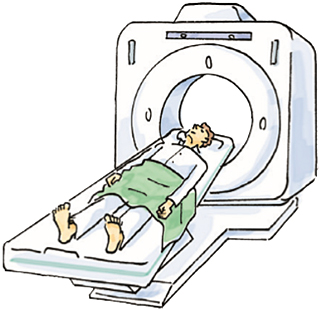

MRI、CT、PET-CT検査

MRIやCT検査、骨シンチグラフィーなどを用いてリンパ節や骨を含めた遠隔転移の有無を診断します。

最近ではPET-CT検査が小さながんの検出や治療後の残存の検索に役立つとする報告もありますが、がんの種類により有用性は異なると言われています。

CT(右精巣腫瘍)

MRI(左精巣腫瘍)